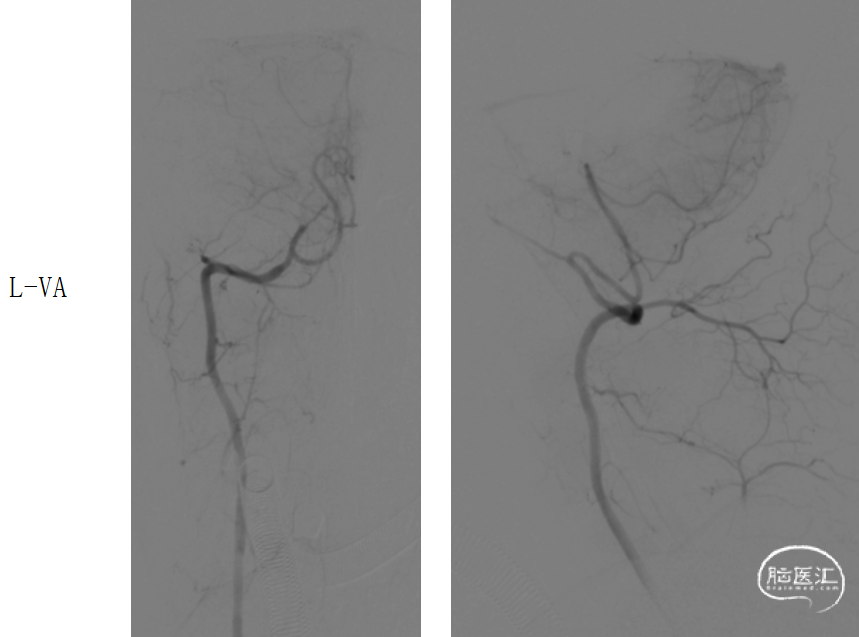

造影示:基底动脉下段可见重度狭窄,远端闭塞,将Catalyst5缓慢通过狭窄处置于闭塞处,负压抽吸可见抽出暗红色血栓,复查造影基底动脉下段重度狭窄,远端显影良好,双侧大脑后动脉、双侧小脑上动脉显影良好,mTICI分级:3级。

在Synchro0.014*300cm微导丝携带下将Gateway2.5*15mm球囊送至基底动脉下段狭窄处,定位准确后,以8atm压力扩张,复查造影,基底动脉下段狭窄略改善,残余重度狭窄。

撤出球囊,将APOLLO3.0*13mm支架沿微导丝送至基底动脉狭窄处,定位准确后以10atm压力释放,复查造影基底动脉显影良好,狭窄处明显改善,无明显残余狭窄,双侧大脑后动脉、双侧小脑上动脉显影良好。

将Catalyst5置于闭塞处,负压抽吸可见抽出暗红色血栓,复查造影基底动脉下段重度狭窄,双侧大脑后动脉、双侧小脑上动脉显影良好。

Synchro0.014*300cm微导丝携带Gateway2.5*15mm球囊至基底动脉下段狭窄处,定位准确后,以8atm压力扩张,复查造影

将APOLLO3.0*13mm支架沿微导丝送至基底动脉狭窄处,定位准确后以10atm压力释放,复查造影。